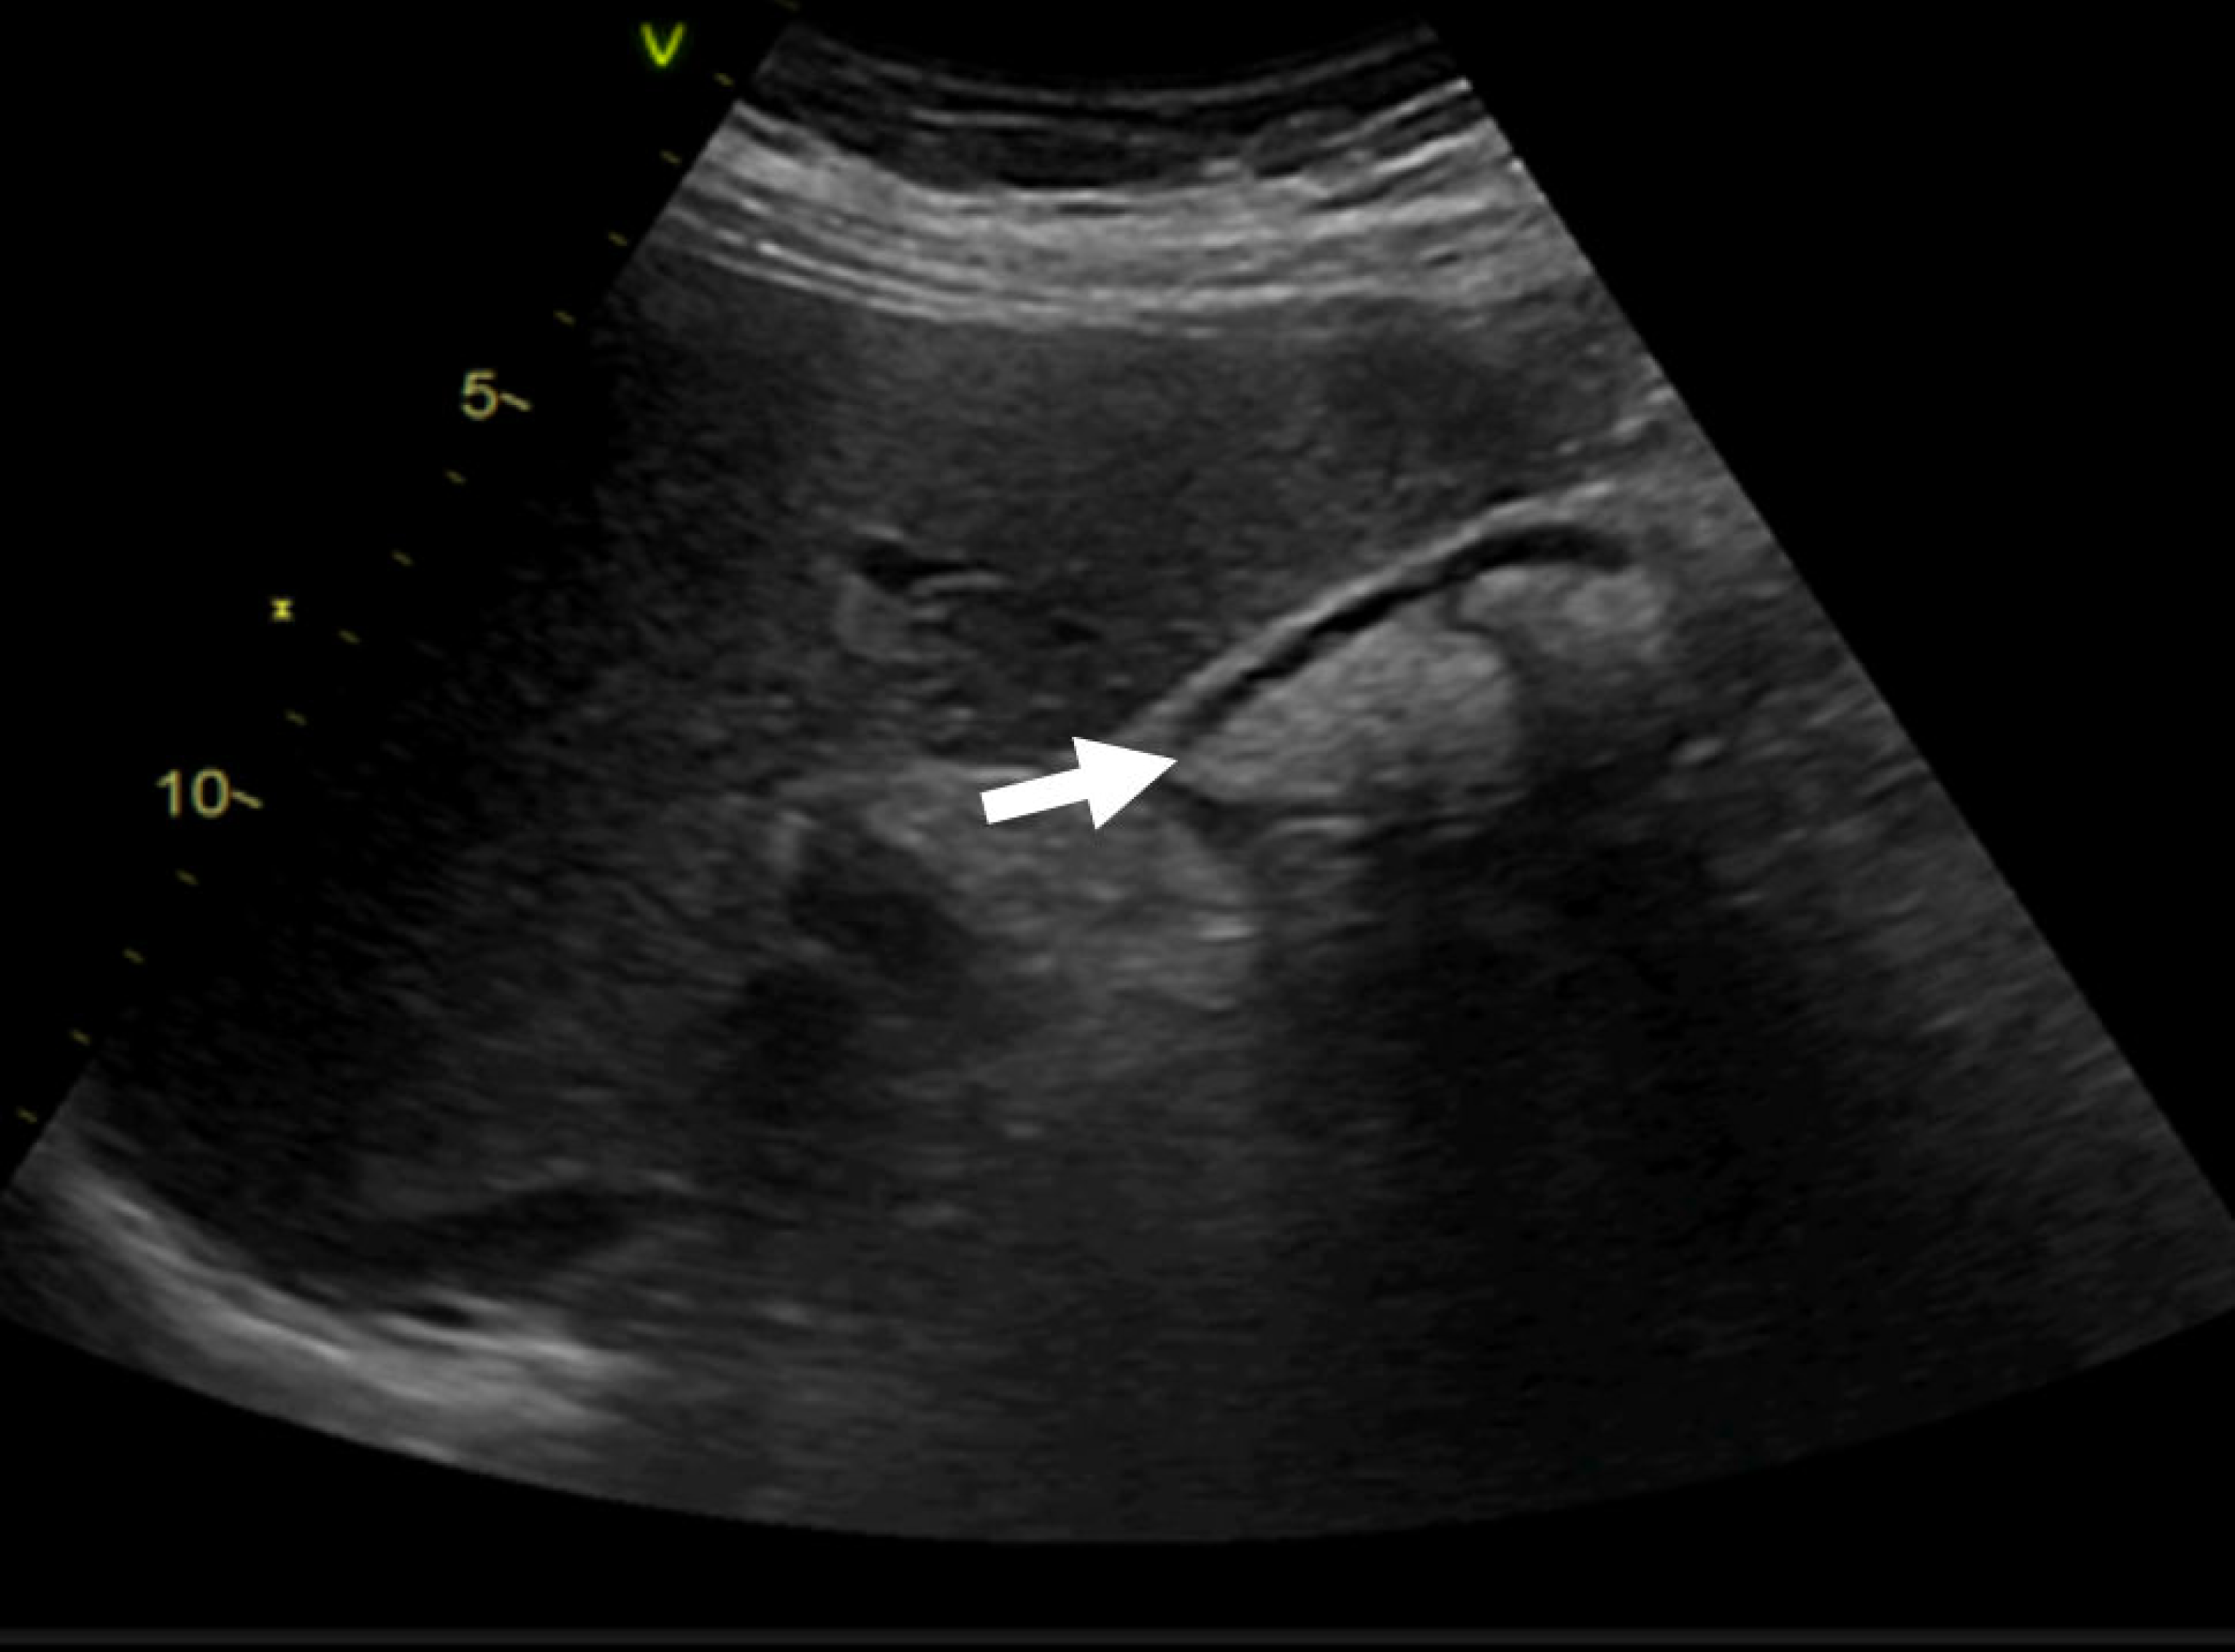

During the hospitalization, the association of severe infection with the myocardium and the saline solution infusion for the antibiotic treatment led to heart failure decompensation with subclinical congestion. The patient was monitored for signs of congestion using systemic ultrasound (inferior vena cava diameter, hepatic veins flow, and renal venous flow) on a weekly basis. Changes in renal venous flow during ultrasound monitoring were suggestive of subclinical congestion. Diuretic therapy with furosemide was initiated with an improvement of/normalized renal venous flow profile, indicative of decongestion (Figure 6).

Figure 6. Right intrarenal-venous flow. In the left image 1, discontinuous intrarenal venous flow with S wave < D wave is observed, while in the right image 2, continuous intrarenal venous flow is seen.